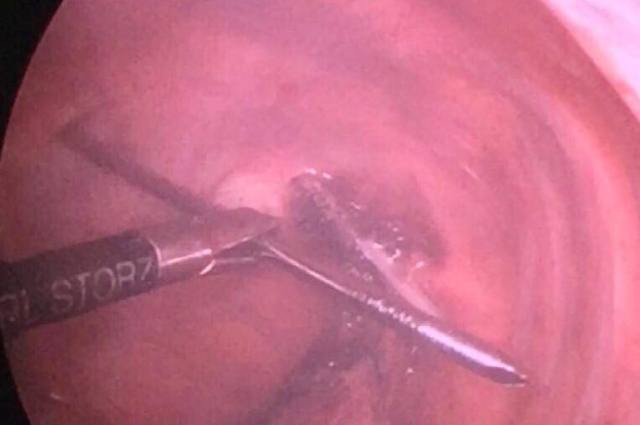

Kíp phẫu thuật phối hợp giữa Chuyên khoa Chấn thương chỉnh hình - Cột sống và Chuyên khoa Phẫu thuật lồng ngực tim mạch, đã quyết định sử dụng phương pháp mổ nội soi để rút đinh, thay vì mổ mở vào lồng ngực như các tác giả nước ngoài.

Tận dụng lợi thế phẫu thuật nội soi ít gây tổn thương thêm cho các phần mềm xung quanh và hình ảnh qua camera được phóng to giúp kiểm soát chảy máu và kiểm soát tổn thương tuỷ sống, dò dịch não tuỷ dễ dàng hơn.

Hình ảnh gỡ chiếc đinh khổng lồ ra khỏi nhu mô phổi (Ảnh BVCC)

"Sau 20 phút vô cùng căng thẳng, chiếc đinh được gỡ ra khỏi nhu mô phổi và nhẹ nhàng rút ra khỏi tuỷ sống một cách an toàn, không gây tổn thương tuỷ sống và hệ thống mạch máu xung quanh tuỷ. Lỗ rút đinh chảy 1 chút dịch não tuỷ được bịt kín lại"- BS. Kiên thông tin.